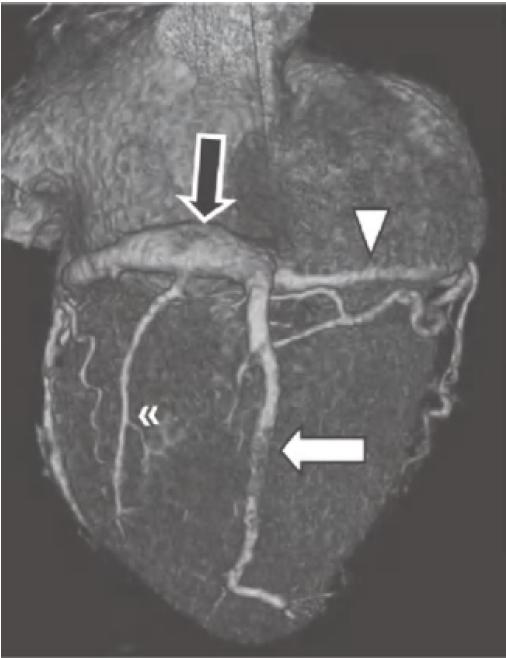

图13-4 RCA优势型,RCA绕过右心缘,在RAVG的下方发出后降支(箭),并走行于后室间沟(虚线)。心中静脉(箭头)也在后室间沟内走行

RCA.右冠状动脉;RV.右心室;LV.左心室

RCA近端分支为圆锥支,绕行在右心室流出道周围。圆锥支及窦房结动脉(另一个近端分支)为右心室流出道、右心房及窦房结供血。有时,这些分支也可能直接起自右冠窦。在右心室缘,RCA通常会发出一条锐缘支,为右心室前壁(或游离壁)供血。

当冠状动脉为RCA优势型时,RCA可走行至RAVG的下部,并发出走行于后室间沟的后降支。在约50%的RCA优势型人群中,还有一条明显的后外侧支,沿LAVG的下半部分走行,供应左心室下外侧壁心肌。这一分支还可能为二尖瓣的下间隔乳头肌供血,因此对其进行准确识别尤为重要。